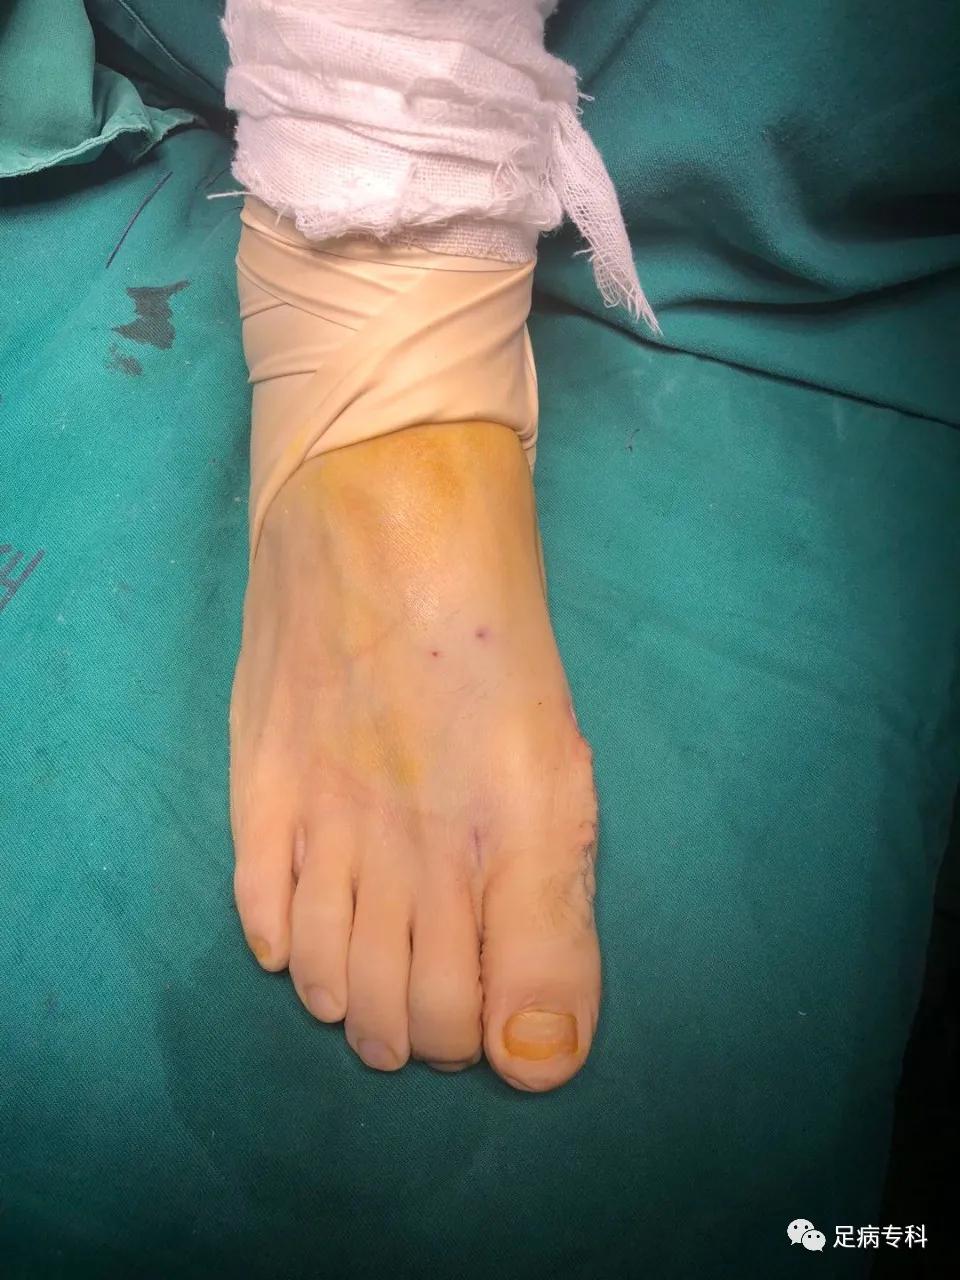

术后包扎

手术方式:双侧Chervon + Akin截骨术(可吸收螺钉固定),拇囊松解+拇内收肌离断术

手术时间:2小时30分。

手术很顺利,手术前做了充分的准备,手术过程全部列了清单,贴在墙上,团队成员提前全部准备好。百密一疏,还是忽略了重要的一点,这次是我是自己给自己做手术,体位改变,右手来离断左脚的拇内收肌和外侧关节囊的时候,不顺手,很折腾了一会。还有就是开始止血带打的不够紧,有少许渗血,大约5毫升,影响到了手术视野。认识到这两个问题,第二只脚就顺利多了,完全没有出血。

手术后我没有觉得不舒适,做完就下地行走了,签字画押,手术室的一套手续做完,坐的轮椅回的病房。